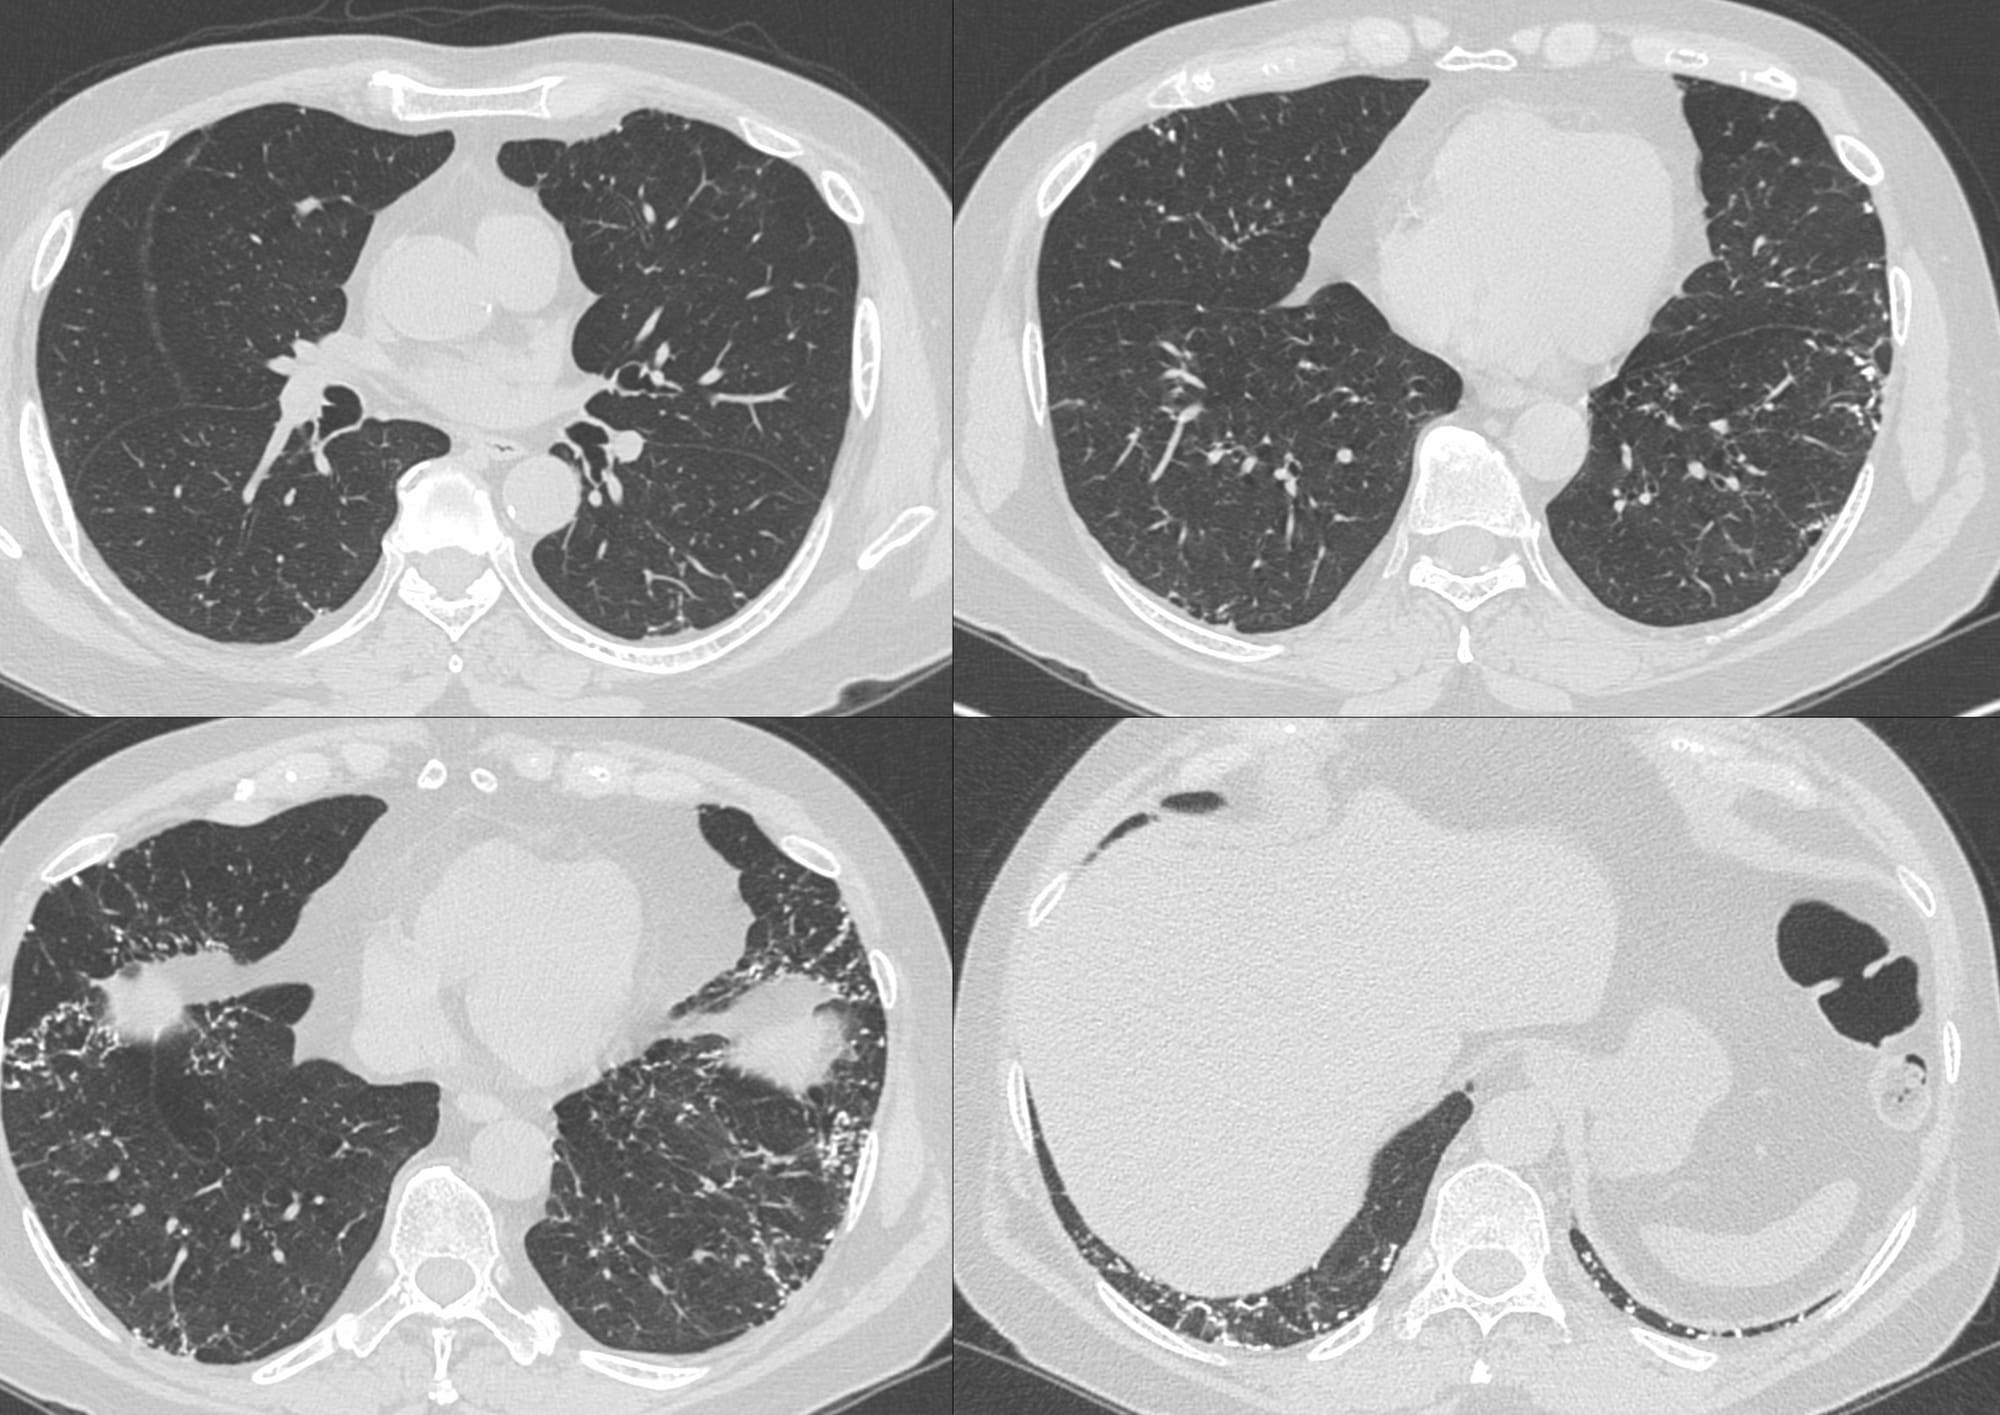

63-years old with a remote 4 pack years history of smoking came with mild dyspnea, and cough with expectoration

20 mm MIPs showed the classic lacy pattern of dendriform diffuse pulmonary ossification (DPO)